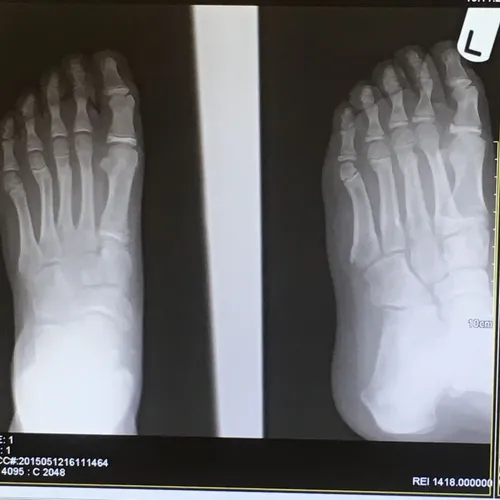

Pediatric Displaced 5th Met Distal shaft/neck fracture

Preop Pics of the displaced fracture prior to Percutaneous Fixation and Reduction

We percutaneously put a pin across the fracture after closed reduction for 12-16 weeks. The last picture is a final after the fracture is healed and the pin is removed.